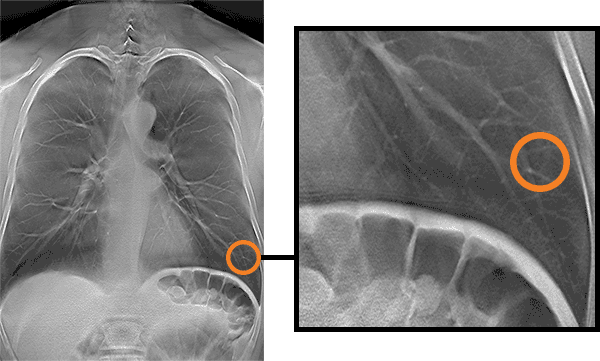

显示病理的 DT 影像层面/显示病理的多个层面